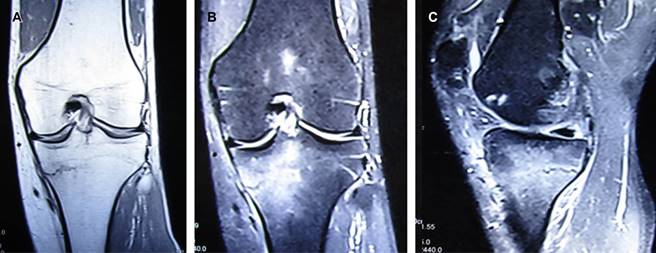

Figura 1: Imágenes de resonancia magnética: (A) ponderada en T1 en plano coronal, mostrando fractura metafisiaria, abarcando 40% del platillo tibial medial; (B) plano coronal en T2 con supresión grasa, mostrando edema óseo en 50% de la porción medial de la metáfisis de la tibia; (C) corte sagital, edema óseo y fractura metafisiaria de tibia derecha sobre vertiente posterior.

Debido al corto tiempo de la lesión se consideraron las posibilidades diagnósticas de: a) lesión de menisco medial (por el mecanismo giratorio de la rodilla); b) fractura de estrés en metáfisis de la tibia (por el tipo y el tiempo de ejercicio efectuado con cambios de velocidad e intensidad en la última semana); c) tendinitis y bursitis anserina (por el mecanismo de lesión). Por lo anterior, se decidió efectuar una resonancia magnética, la cual mostró fractura de estrés metafisaria de la tibia, no desplazada, que abarcaba el 40% de ésta (Figura 1).